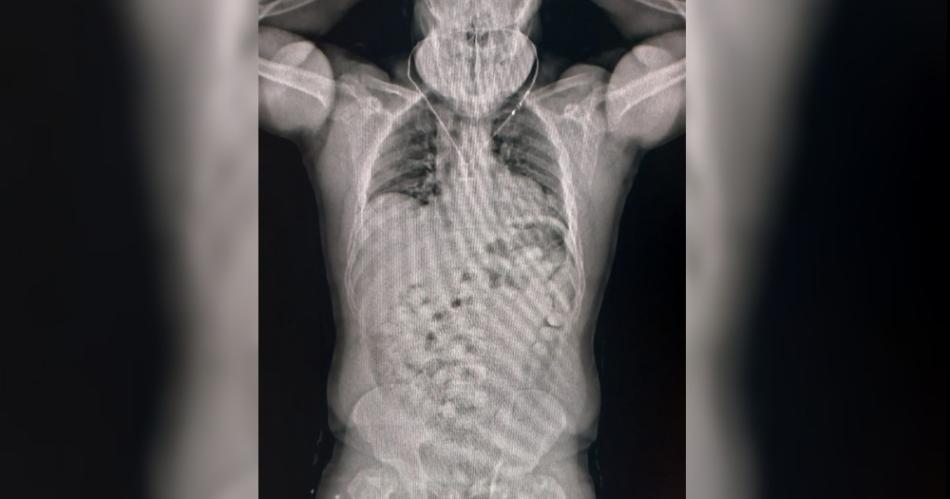

Ante todos los indicios, los guardas inspeccionaron su equipaje pero no encontraron nada. Dado que las dudas persistían, decidieron utilizar otro método de control: el body scan. Las imágenes confirmaron las sospechas del personal aduanero dado que mostraban cuerpos extraños.

Ante la posibilidad de que se tratase de un método de ocultamiento de estupefacientes, se internó al pasajero en un centro médico y lograron confirmar que había ingerido cápsulas con droga. En total eran 84 y contenían 1134 gramos de cocaína que en el país de destino se podría vender a USD 51 mil.